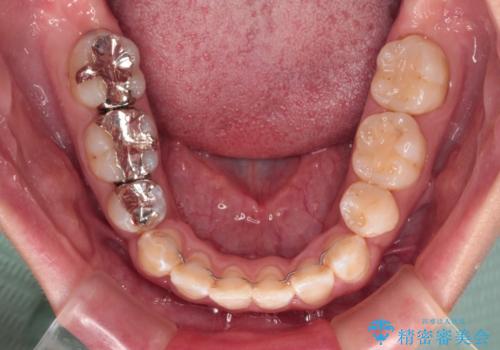

- 前歯のクロスバイトと、口元が閉じにくいとのことで来院された患者様です。

口元の突出感を改善する必要があるため、上下左右の第1小臼歯4本を抜歯し、ワイヤー装置にて矯正治療を行うこととしました。

むし歯のリスクが高かったため、治療が長期化しないように心がけました。

当初の予定通り、2年強で無事に治療を終えることができました。